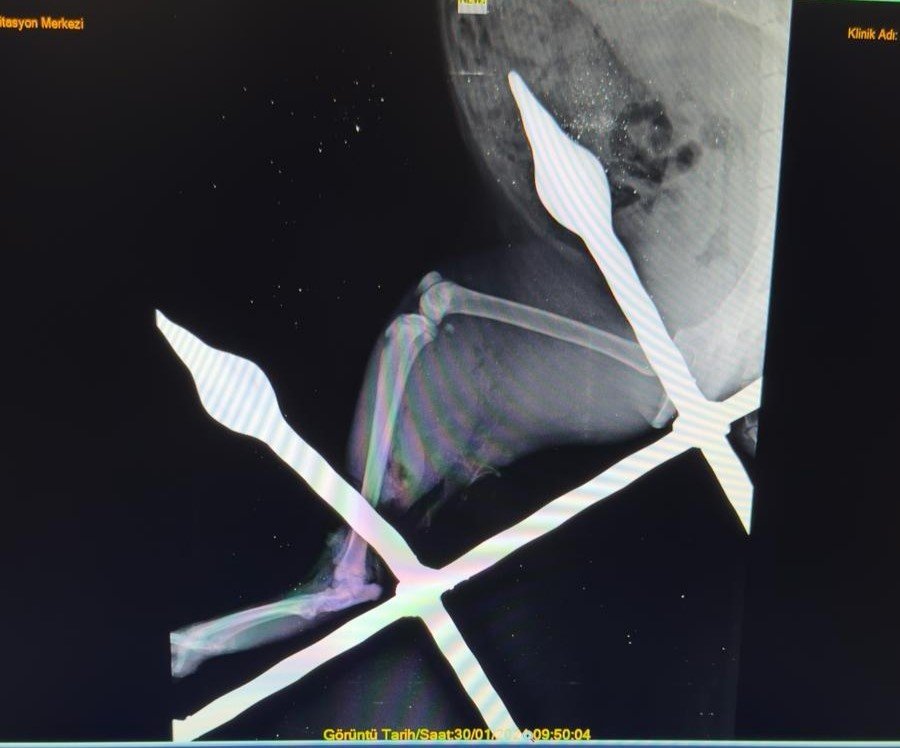

Yaralı kedinin bacağını eski sağlığına kavuşturduklarını anlatan Mersin Büyükşehir Belediyesi Tarımsal Hizmetler Dairesinde Veteriner Hekim olarak görev yapan Yusuf İncir, "Yapılan ilk tespitler sonucunda, balkon demirinin bacağından yaklaşık 10-15 santimetre civarında geçtiği görülmüştür. Yapılan dezenfeksiyon ve temizlik işlemlerinin ardından, balkon demiri anestezi altındaki kedinin bacağından çıkarıldı. Çıkarılırken dokuya mümkün olduğu kadar zarar vermemeye dikkat ettik. Yaptığımız tespitlerde kaslardan bir tanesinin kopmuş olduğu, yalnız sinir dokusunda herhangi bir hasar oluşmadığı tespit edilmiştir. Yapılan yara temizliği ve dezenfeksiyonun ardından, kopan kas kısmı dikişle tekrar eski haline getirildi. Dezenfeksiyonun ardından, yırtılan ve hasar gören dokuların dikiş işlemini gerçekleştirdikten sonra, deri dikişi ile işlemimizi tamamladık. 12 gün zarfında kedimiz sağlığına kavuştu" ifadelerine yer verdi.